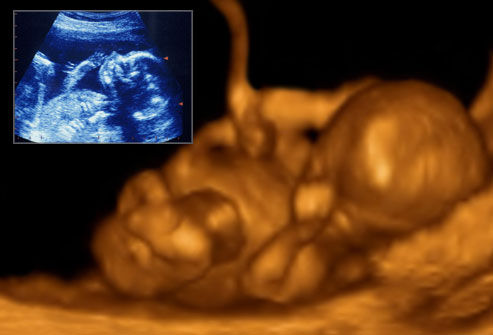

现在小编将整理出的胎儿发育图呈现给大家:

一个月:每一个月新生命的成长比任何时期都快,要比受精卵长大一万倍。动脉、静脉已形成,且有血液流动;脑、肾、消化管已见雏形;脐带已开始工作;心脏形成且开始跳动。

两个月:胚胎外形已初步具备了人的模样。头占全身的一半,胚胎颜面已显现出来,有舌及尚未成熟的牙床,臂上 已有手指,腿上有了膝盖、足踝和脚趾,胚胎全身覆盖着一层薄薄的皮肤;大脑和性器官都开始发育,心脏跳动稳定,胃开始分泌消化液,肝脏开始制造血细胞;肾 脏已开始工作,可排出血中的尿液;皮肤敏感性增强,对触觉刺激可做出反应。

三个月:胎儿的器官系统开始工作,可以呼吸也可以排泄,胎儿身长约6~10厘米,体重50克左右,外生殖器已开始发育,嘴能张、合,吞咽,四肢可以活动;对外界刺激可以发生反应,如果碰碰他的眼睑,他会眯一下眼睛;碰碰他的手掌,手指可弯曲;碰碰他的嘴唇,他 会咂一下嘴;碰足跟,脚趾会张成扇形。

四个月:胎儿身长约13~17厘米,体重125克左右;骨骼系统进一步发育,胎盘已完全形成;胎儿四肢活动力增强,母亲可感到胎动,肌肉有所发育。

五个月:头上长出了细茸的头发,眉毛和眼睫毛也长出来了,像绒毛似的胎长覆盖全身;身长20~30厘米,体重250~300克;在子宫里取得一个适宜的位置;如果把耳朵紧贴母亲腹部,可以听到胎儿的心跳。

六个月:胎儿身长33厘米左右,体重600~700克;皮下开始有脂肪;眼睛已完全长好,可以睁开和闭拢,还可环视周围,可正常呼吸,还有哭的表情,手可以攥成拳头

七个月:胎儿身长约40厘米,体重可达1000克,各器官发育齐全,已初步具备了生活能力。

八个月:胎儿身长已长到43厘米,体重1750克左右,这时生长很迅速,几乎充盈整个子宫;由于活动空间变小,胎儿活动减少;胎儿皮下逐渐长出脂肪,准备适应子宫外的气温变化。

九个月:胎儿身长已长到50厘米,体重达2500克左右,如果在这时出生,存活机会较大。

十个月:胎儿发育成熟,叫足月胎儿或成熟儿。临产时新生儿的体重平均在3000克左右,身长达50厘米左右,如果降临人世,那清脆的哭声、活泼的四肢运动、强烈的哺乳欲求、光滑细腻的皮肤,显示了无比强盛的生命力。